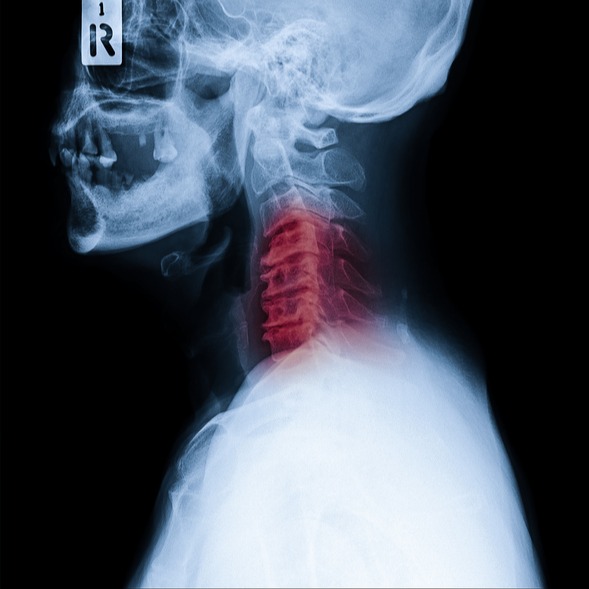

• imaging: gli esami di imaging sono essenziali per la diagnosi delle anomalie cranio-cervicali. Le tecniche di imaging che possono essere utilizzate includono la radiografia, la tomografia computerizzata e la risonanza magnetica. Questi test possono mostrare dettagli sulla struttura ossea, sulle articolazioni e sulla posizione delle strutture nervose nella regione cranio-cervicale;